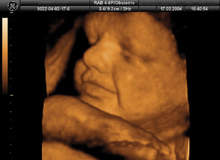

As well as enabling diagnosticians a unique ability to examine foetal structures with higher accuracy, for expectant parents, these scans allow a bonding experience unlike any other – complete with the option to download keepsake photos and videos on to a mobile phone or MP3 player.

In 3D ultrasound, a transducer takes a series of images of the foetus, which are then processed through a computer and rendered as a 3D image. These images can then be rendered in rapid succession, creating an almost real-time animation known as 4D. The technologies themselves are far from new – 3D ultrasound was introduced in 1989 with 4D emerging in 1998 – but from a clinician's perspective, current technology is well ahead of its predecessors and allows for far better diagnostic precision.

"Social or elective 3D/4D ultrasounds can provide images that are more readily recognised by parents-to-be, which helps enhance maternal and paternal bonding," says Horn. "The 4D application also provides the added opportunity to see the unborn baby's real-time movements and therefore movements like facial expressions, swallowing and even blinking can sometimes be visible. In my experience, parents thoroughly enjoy seeing these more life-like pictures and these scans are growing in popularity."

Unlike 2D ultrasound, which looks through structures, 3D/4D technology composites three different angles of images into solid structures, which mean that anything in front of the baby, such as an anterior placenta, will obscure the view. It is generally accepted that the best time to have a 3D/4D scan is between 26 and 28 weeks of pregnancy because the baby is putting on more fat and will have the classic "chubby cheek" look, but there is still ample room within the uterus to obtain optimum image results.

Perhaps the most enticing part of a 3D/4D ultrasound scan is the ability for expectant parents to take the images with them. Elective 3D/4D scans have been indispensable in creating stronger bonds between mother and baby. Seeing real-time footage of the unborn child helps to solidify the pregnancy and has been shown to affect how the mother cares for herself through her life choices.